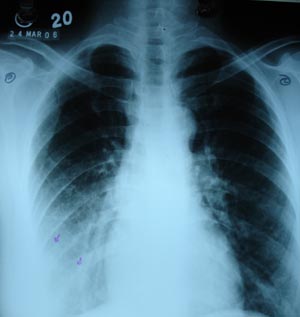

Right lower zone opacity 2

Though the opacity of right lower zone is not uniform, but obliteration of right costophrenic angle & crescent shape opacity is suggestive of pleural effusion. Pneumonic opacity would have left the costophrenic angle untouched.